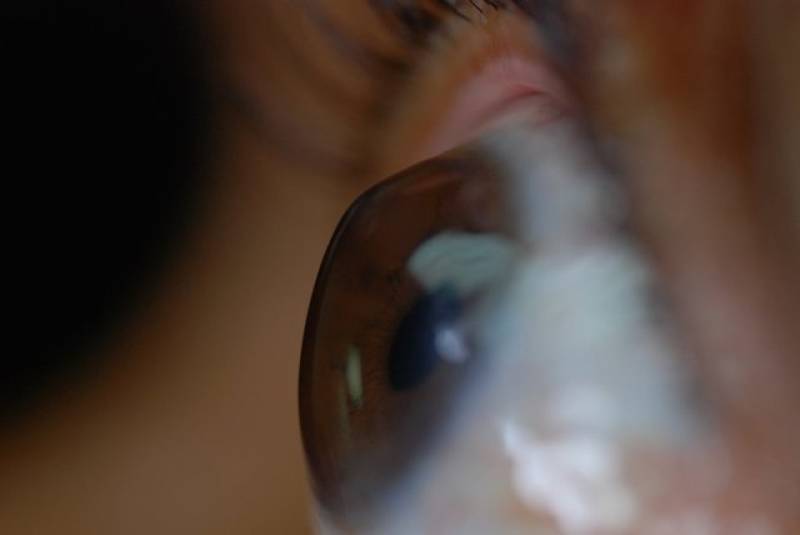

با تشخیص به‌موقع قوز قرنیه، نیاز به پیوند ندارید

یک جراح ومتخصص چشم:

با تشخیص به‌موقع، کنترل و درمان قوز قرنیه می‌توان از پیشروی و پیوند قرنیه پیشگیری کرد.